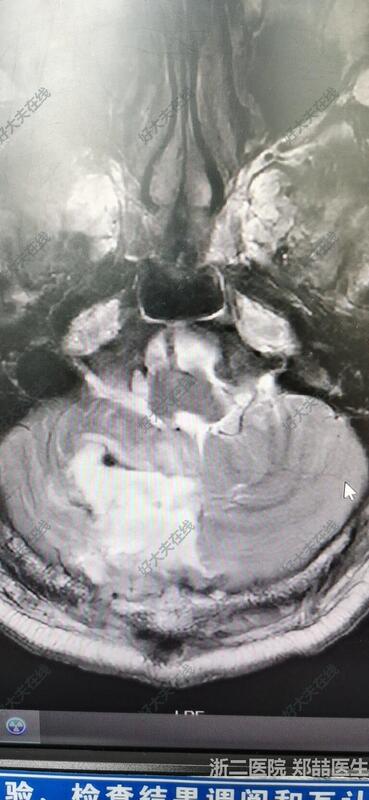

患者恢复良好,可下地活动,头晕好转,无其他不适。头磁共振复查提示肿瘤全切。